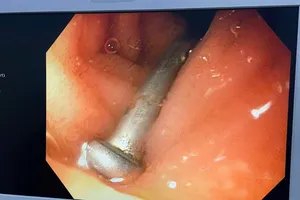

Gắp cây đinh sắt 3cm trong tá tràng bé trai 6 tuổi ở Quảng Ngãi